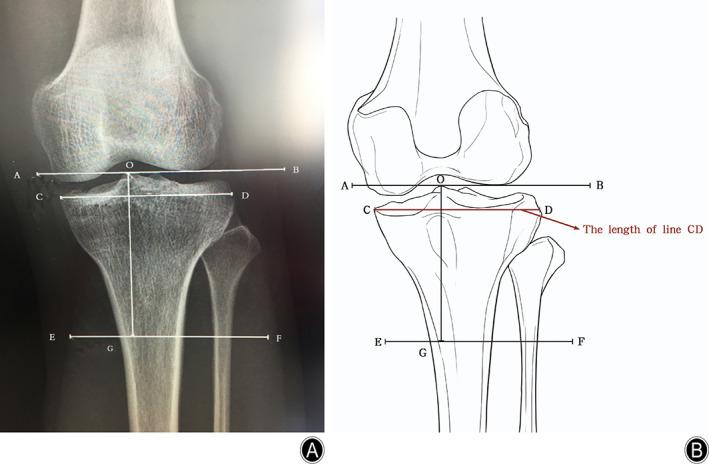

To propose an updated definition of proximal tibia and fibula fracture (PTFF) and establish a three-dimensional (3D) structure-based classification of PTFF.

In total, 1358 adult patients (837 males and 521 females; 43.61 ± 15.13 years, 1364 affected knees) who were diagnosed with PTFF at the departments of orthopaedic surgery of four hospitals from January 2010 to December 2019 were enrolled. The new classification of PTFF, termed Wu classification, included three parts: classification of columns in the horizontal plane, regions in the frontal plane, and segments in the sagittal plane. All PTFFs were classified according to Schatzker, Luo, and Wu classification systems. Additionally, the incidence and characteristics of PTFFs were analyzed.

The major internal structural fractures of PTFF were tibial plateau fracture (TPF) only (725, 53.15%), TPF and proximal fibular fracture (274, 20.09%), and isolated avulsion fracture of the posterior cruciate ligament (PCL) (189, 13.86%). Approximately a quarter of PTFF cases could not be classified using Schatzker or Luo classifications, but all PTFF cases could be classified using Wu classification. The most frequent PTFFs included all four columns in region IV, segment 2 (235, 17.23%); the posterolateral and posteromedial columns in region II, segment 2 (191, 14.00%); and the lateral and posterolateral columns in region IV, segment 2 (136, 9.97%). Isolated avulsion fracture of the anterior cruciate ligament (ACL) was categorized as three injury types, most of which involved the lateral and medial columns in region II, segment 1 (40/63, 64%). More than 97% of cases of isolated fractures of the PCL involved the posterolateral and posteromedial columns in region II, segment 2. The most frequent combined avulsion fracture of the ACL and PCL included all four columns in region II, segment 2 (18/24, 75%). All of the isolated avulsion fractures of the ACL were located in segment 1, and all those of the PCL in segment 2. The most common type of isolated proximal fibular fracture involved the posterolateral column in region III, segment 2 (23/26, 88%). The most frequent combined TPF and proximal fibular fracture involved all four columns in region IV, segment 2 (107/274, 39.05%).

All cases of PTFF could be classified by the new 3D Wu classification which should be beneficial for clinical diagnosis, guidance of treatment, statistical analysis, academic communication, and prognosis, and the most frequent PTFF involved all four columns in region IV, segment 2.